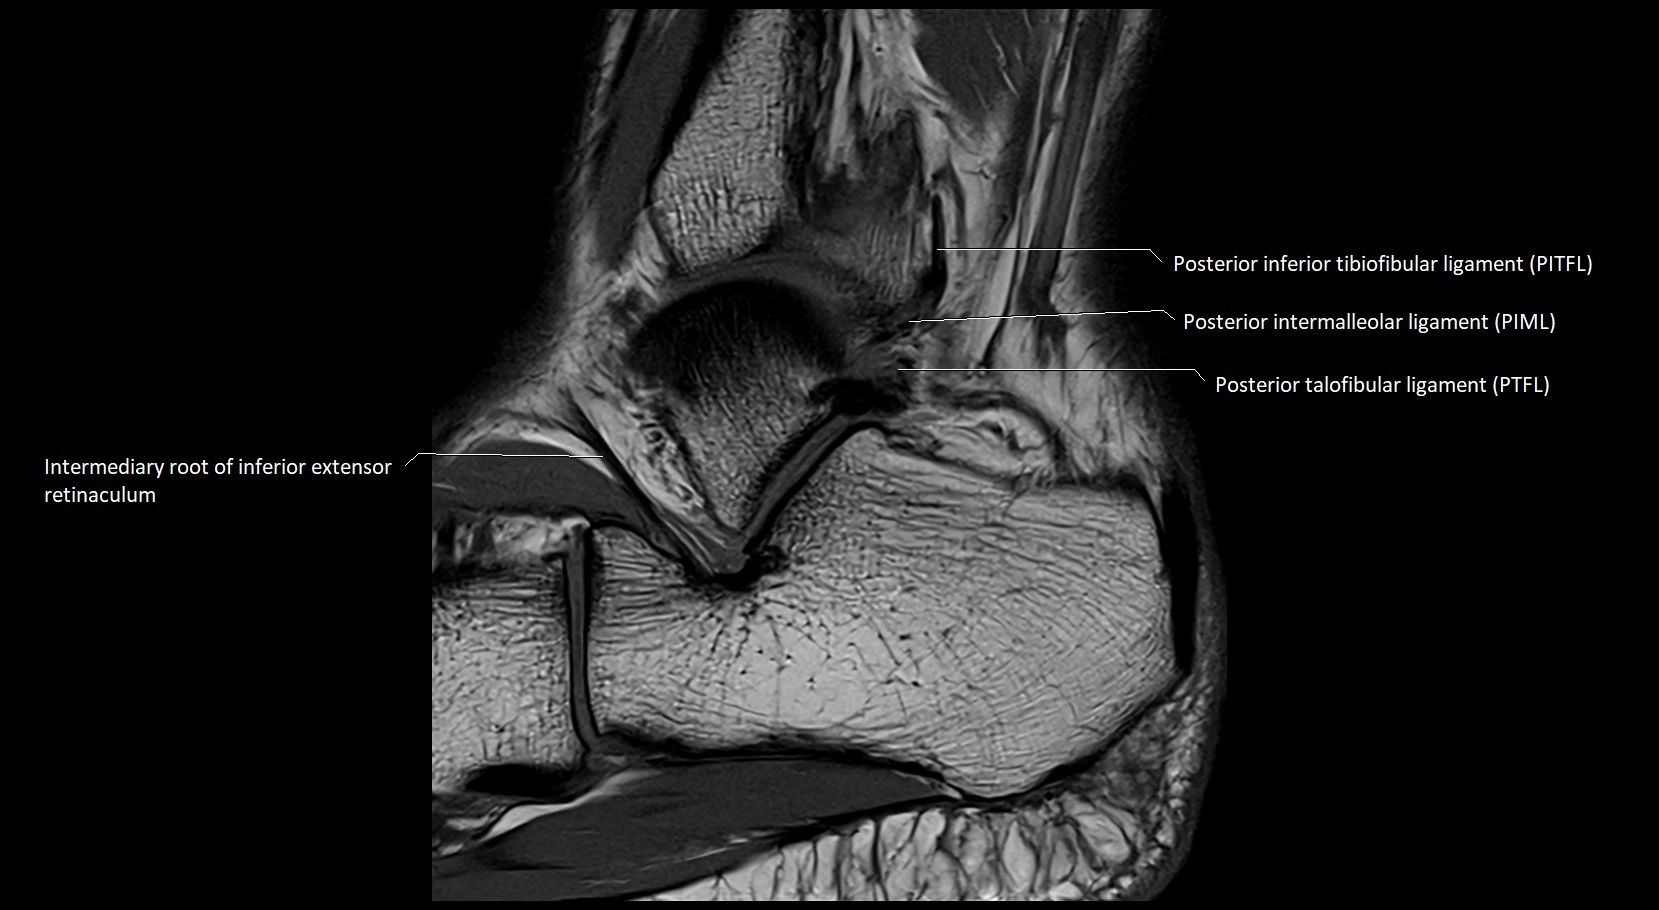

MRI image

image